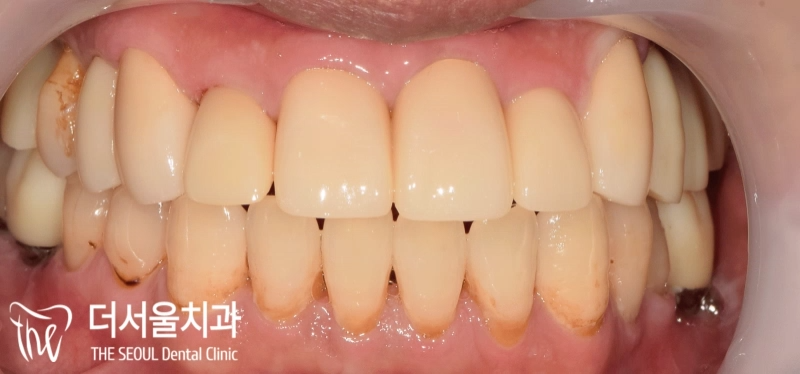

반갑습니다, 여러분~ 더서울치과 박현준 원장입니다. 치아에 썩은 곳이 많거나 빠져버린 곳이 많은 분들은 어디서부터 손을 대야 될지 몰라 고민을